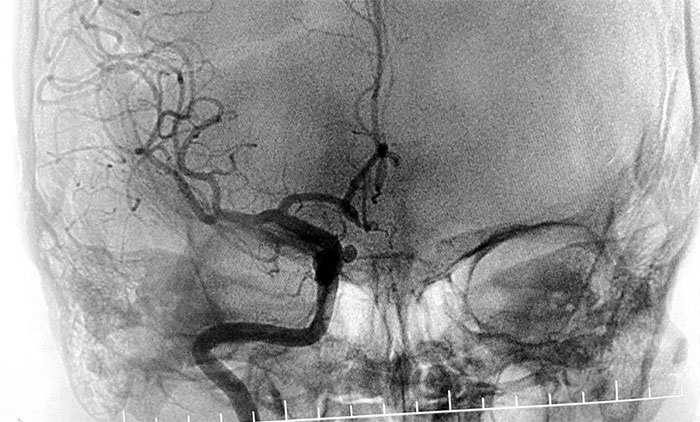

患者入院后,余志良主任為患者完善查體,根據(jù)病情特點,著重排查腦血管疾病可能。通過CTA檢查,發(fā)現(xiàn)右側(cè)頸內(nèi)動脈C6段動脈瘤。醫(yī)院學(xué)術(shù)副院長、神經(jīng)內(nèi)科4A病區(qū)主任席剛明教授團隊進一步行DSA腦血管造影檢查,提示右頸內(nèi)動脈眼動脈段動脈瘤。

▲ DSA檢查提示,右頸內(nèi)動脈眼動脈段動脈瘤

通過審慎討論評估,余志良主任和席剛明教授一致認為,該部位動脈瘤可因壓迫重要血管神經(jīng),引起頭痛頭暈、視覺障礙等相關(guān)癥狀。一旦發(fā)生破裂出血,可導(dǎo)致患者出現(xiàn)一系列嚴重的神經(jīng)功能損害,甚至危及生命。

患者頭痛癥狀明顯加重,結(jié)合動脈瘤形態(tài)及相關(guān)檢查,瘤體破裂風(fēng)險較高,建議積極治療。該動脈瘤較理想的治療方式為血流導(dǎo)向裝置置入,它具有手術(shù)微創(chuàng),相較于其他手術(shù)方式,減少對瘤體本身的擾動,安全性相對更高,在降低和防止動脈瘤遠期復(fù)發(fā)等方面也具有一定的優(yōu)勢。經(jīng)討論,大家一致認同該治療方案,與家屬詳細解釋溝通后,同意進行手術(shù)治療。

經(jīng)充分完善術(shù)前準備,席剛明教授在麻醉科和介入手術(shù)室緊密配合下,開展右頸內(nèi)動脈眼動脈段動脈瘤血流導(dǎo)向裝置(Pipeline)置入術(shù)。手術(shù)歷時兩個小時,順利“拆除”了埋在患者腦子里的“不定時炸彈”。